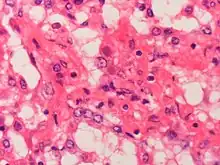

Adenovirus can cause severe necrotizing pneumonia in which all or part of a lung has increased translucency radiographically, which is called Swyer-James Syndrome.[21] Severe adenovirus pneumonia also may result in bronchiolitis obliterans, a subacute inflammatory process in which the small airways are replaced by scar tissue, resulting in a reduction in lung volume and lung compliance.[21]

Dogs can be affected by adenovirus infection.[24] Severe liver damage is a classical infectious disease seen in unvaccinated dogs.[25]